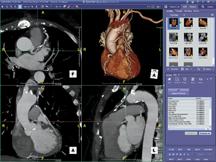

Volumetric data produced from multislice CT and MR systems provide valuable insight for clinicians, especially within the cardiac arena where the number of images required to diagnose and treat a single patient can range from tens to thousands.

March 10, 2009 - ProSolv CardioVascular, a FUJIFILM company, has released its newest software version Synapse ProSolv cardiovascular 4.0.1, featuring an integrated ECG management capability and integration with the Siemens Sensis Hemodynamic system. Synapse ProSolv cardiovascular 4.0.1 will be one of several new products highlighted at ACC 2009 this month.